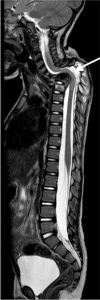

Tuberculosis (TB) remains one of the major public health threats worldwide, despite improved diagnostic and therapeutic methods. Tuberculosis is one of the main causes of infectious disease in the chest and is associated with substantial morbidity and mortality in paediatric populations, particularly in low- and middle-income countries. Due to the difficulty in obtaining microbiological confirmation of pulmonary TB in children, diagnosis often relies on a combination of clinical and radiological findings. The early diagnosis of central nervous system TB is challenging with presumptive diagnosis heavily reliant on imaging. Brain infection can present as a diffuse exudative basal leptomeningitis or as localised disease (tuberculoma, abscess, cerebritis). Spinal TB may present as radiculomyelitis, spinal tuberculoma or abscess or epidural phlegmon. Musculoskeletal manifestation accounts for 10% of extrapulmonary presentations but is easily overlooked with its insidious clinical course and non-specific imaging findings. Common musculoskeletal manifestations of TB include spondylitis, arthritis and osteomyelitis, while tenosynovitis and bursitis are less common. Abdominal TB presents with a triad of pain, fever and weight loss. Abdominal TB may occur in various forms, as tuberculous lymphadenopathy or peritoneal, gastrointestinal or visceral TB. Chest radiographs should be performed, as approximately 15% to 25% of children with abdominal TB have concomitant pulmonary infection. Urogenital TB is rare in children. This article will review the classic radiological findings in childhood TB in each of the major systems in order of clinical prevalence, namely chest, central nervous system, spine, musculoskeletal, abdomen and genitourinary system.